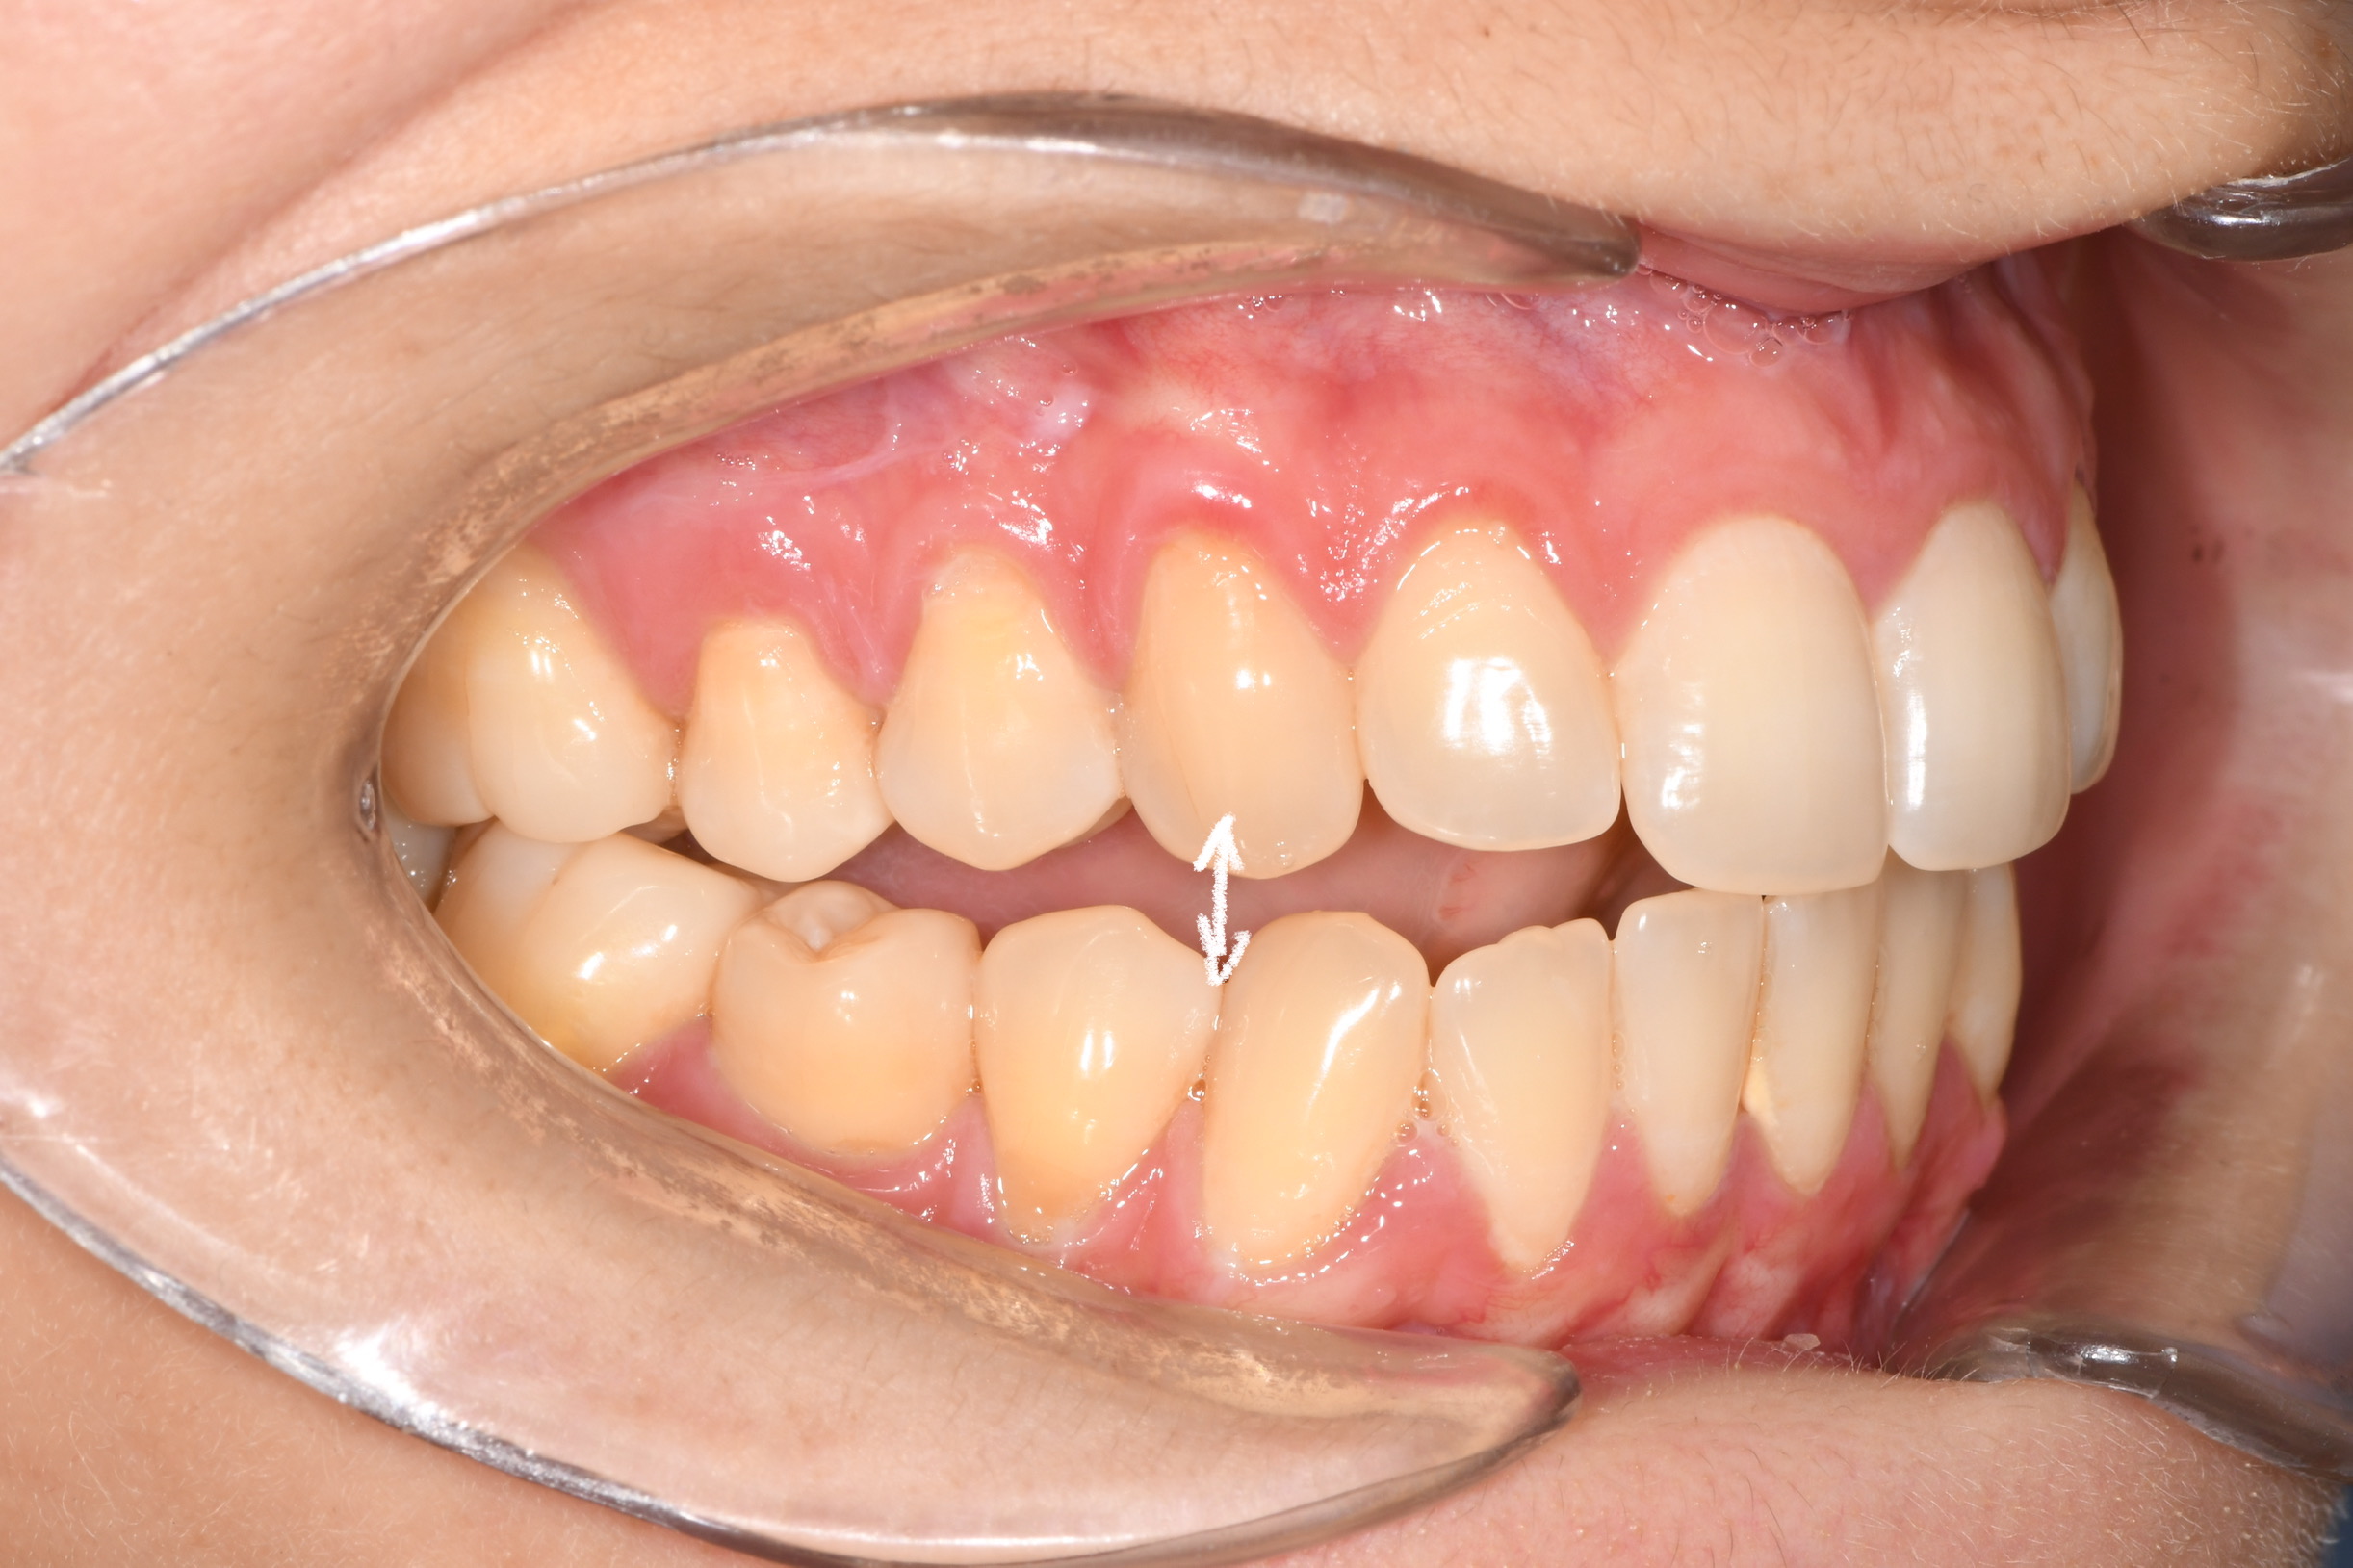

Az elmúlt évekből rengeteg szakmai referenciát tudnánk bemutatni, amelyek különböző fogszabályozási problémákat oldottak meg. Válogatva a több száz esetből, ezen az oldalon olyan képeket, információkat igyekeztünk bemutatni, amelyeknek a segítségével a jövőbeni pácienseinknek azt tudjuk üzenni: A Te fogsorod is lehet gyönyörű!

(Képeket a Pácienseink külön írásos beleegyezésével mutatjuk be!)